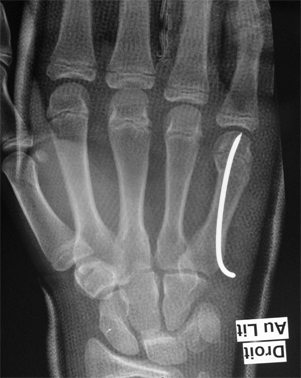

Elles

sont les plus fréquentes des fractures des métacarpiens

et surviennent essentiellement suite à un coup de poing : fractures

dites "du boxeur".

Ces

fractures sont souvent déplacées, avec une bascule du fragment

cassé vers l'avant (la paume de la main).

En

dessous de 30° de déplacement, ces fractures sont seulement

immobilisées sans les remettre en place, et le résultat

sur la fonction de la main est excellent.

Au dessus de 30° de déplacement, une réduction

orthopédique sous anesthésie générale

est souhaitable, suivie d'une immobilisation plâtrée.